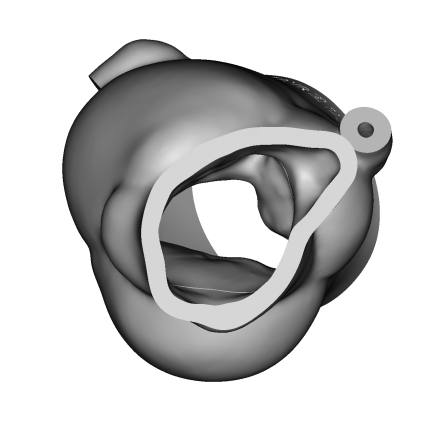

个性化3D打印模型:

3D打印体外模拟:

体外模拟植入29mmJ-Valve瓣膜,升主动脉侧(左图)观察可见定位键挂于无冠瓣上导致瓣架无法到达瓣环位置,左室流出道侧(右图)观察可见瓣架底端距离瓣环平面18mm,且J-Valve在瓦氏窦中呈倾斜状态。